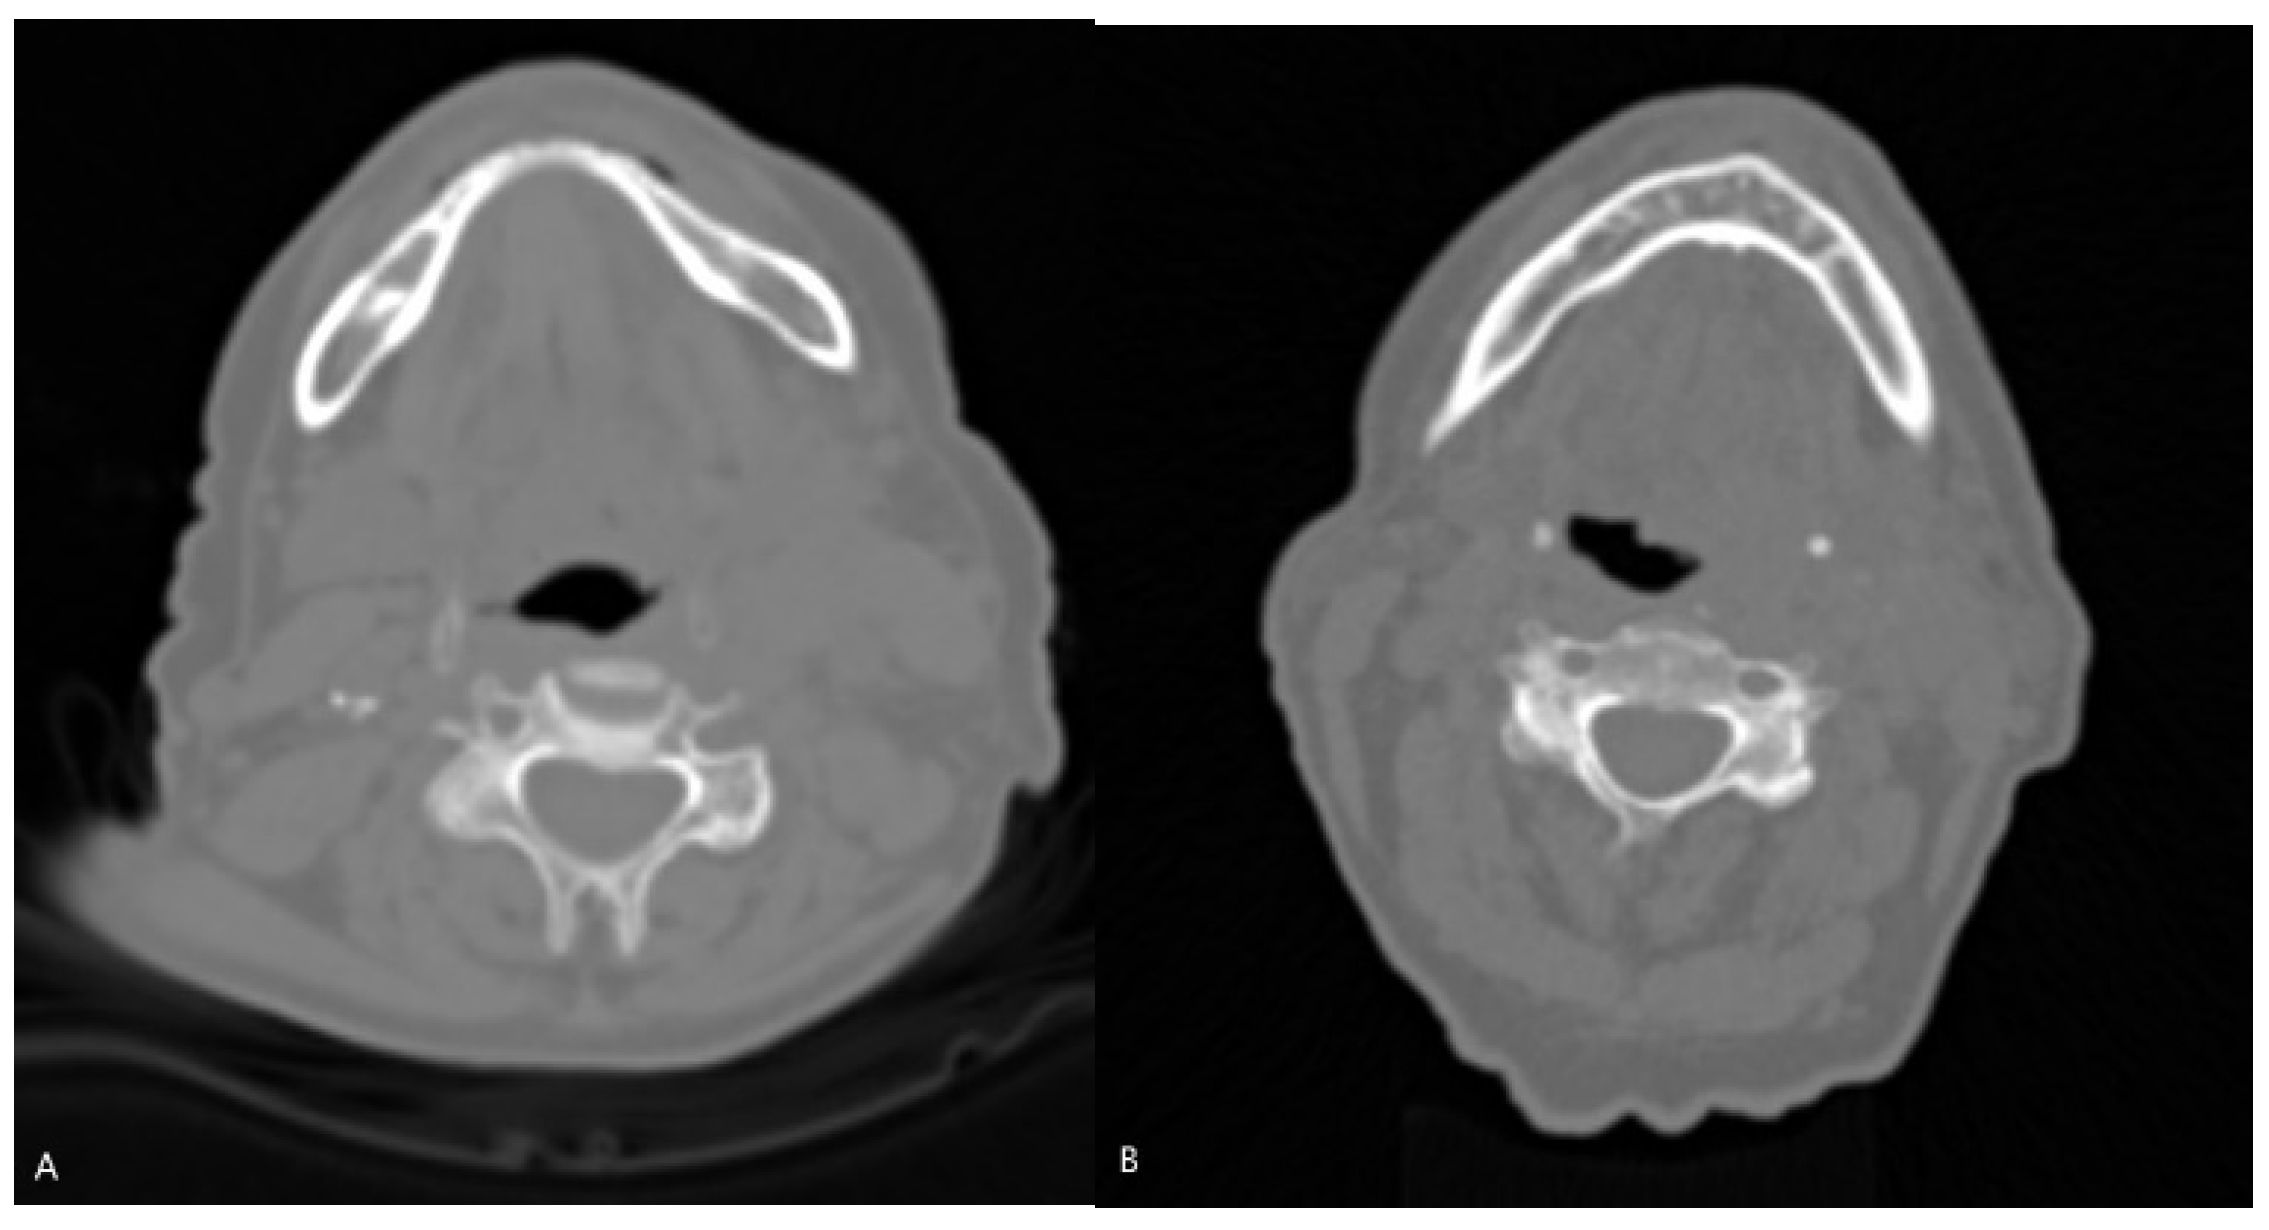

CT data were organized in an NIfTI format for convenient data management. 3D Slicer [16], which is a free and open-source software platform used for medical image processing and visualization, was used for radiomics extraction. 3D Slicer’s segmentation tools, and more specifically, the segment editor, was used to manually delineate regions of interest (ROIs) that needed to be analyzed. In this case, the ROI was the wider area of the oropharynx, and the segmentation was performed on ten slices and for every patient in the dataset. Those ten slices were chosen from the area of HNC, based on the malignancy, as well as on the probable position of lymph nodes. The area was not segmented in detail, but in a wider cubic region of interest (ROI), aiming to develop a method that will save time from clinicians using fixed ROIs (Figure 2). In Figure 3, CT slices from an HPV-positive and an HPV-negative patient are presented. As shown in Figure 2, the manual segmentation of the ROI was performed in one of the ten slices of these patients.

Starting with the CT-based model, as presented in Table 2 and Table 3, the model correctly predicts 90% of the cases and also captures all the instances of actual HPV positivity, achieving an accuracy of 90% and recall of 100%, respectively. In the context of HPV diagnosis, it is very important to ensure that positive cases are not missed. In addition, when the model predicts HPV positivity, it is correct 80% of the time, being reliable in positive predictions, and the F1-score of 0.89 suggests a good balance between precision and recall. Overall, the CT-based model appears to perform well, being a useful tool in medical diagnosis concerning HPV status identification. This performance could be attributed to several factors, such as the detailed and rich information provided by the CT data that enables the model to capture complex patterns related to the HPV status. Moreover, as shown in Figure 2, usually, there is no obvious clinical evidence in CT slices, concerning the HPV status, that can be easily observed with the naked eye, and it seems like this model can be used as a supplementary method in this kind of task. In addition, it can be stated that DL architectures, like ResNet-18, are capable of not only learning hierarchical and complex representations by the input data but also automatically learning relevant features directly by the raw CT data. This kind of model appears to be suitable for medical imaging classification tasks.

Figure 3. Representative slices of patients. (A) An HPV-negative 59-year-old woman. (B) An HPV-positive 74-year-old man.